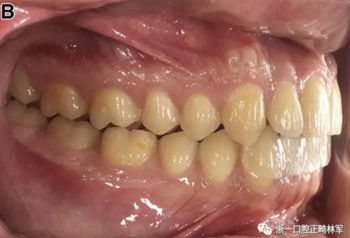

在CBCT成像的一段時間內(nèi),將這個部分薄板放置在前牙上,要求患者習(xí)慣自己的牙齒直到與相對的上頜牙齒發(fā)生接觸。這使得上頜和下頜牙齒之間存在1mm的間隔。沒有下頜偏離或突出應(yīng)該保證下頜的正中關(guān)系。檢查尖牙的關(guān)系,以及上下中線的是否重合。然后對患者進(jìn)行掃描(圖4)。